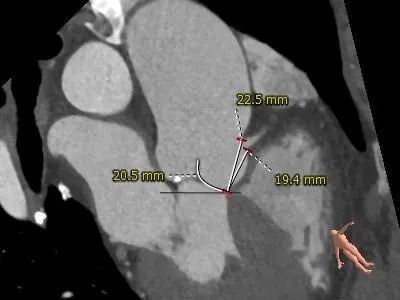

主动脉根部测量:

Type 0 型二叶式主动脉瓣,横位心

冠脉开口高度可,切线角度测量,左窦瓣叶长于左冠开口下缘

•Type 0 型二叶式主动脉瓣,瓣叶增厚,轻度钙化,钙化分布于两侧对合缘;LVOT近似直筒型

•冠脉开口高度可,切线角度测量,左窦瓣叶长于左冠开口下缘

•主动脉瓣水平夹角约60°,横位心,主动脉弓宽度角度可,弓顶部散在附壁钙化

•预装AV26瓣膜,建议瓣环下零位左右定位释放,横位心,升主有扩张,弓部宽度角度可,预计输送器可顺利过弓,若跨瓣困难,备snare辅助;弓顶 部附壁钙化,注意小心通过